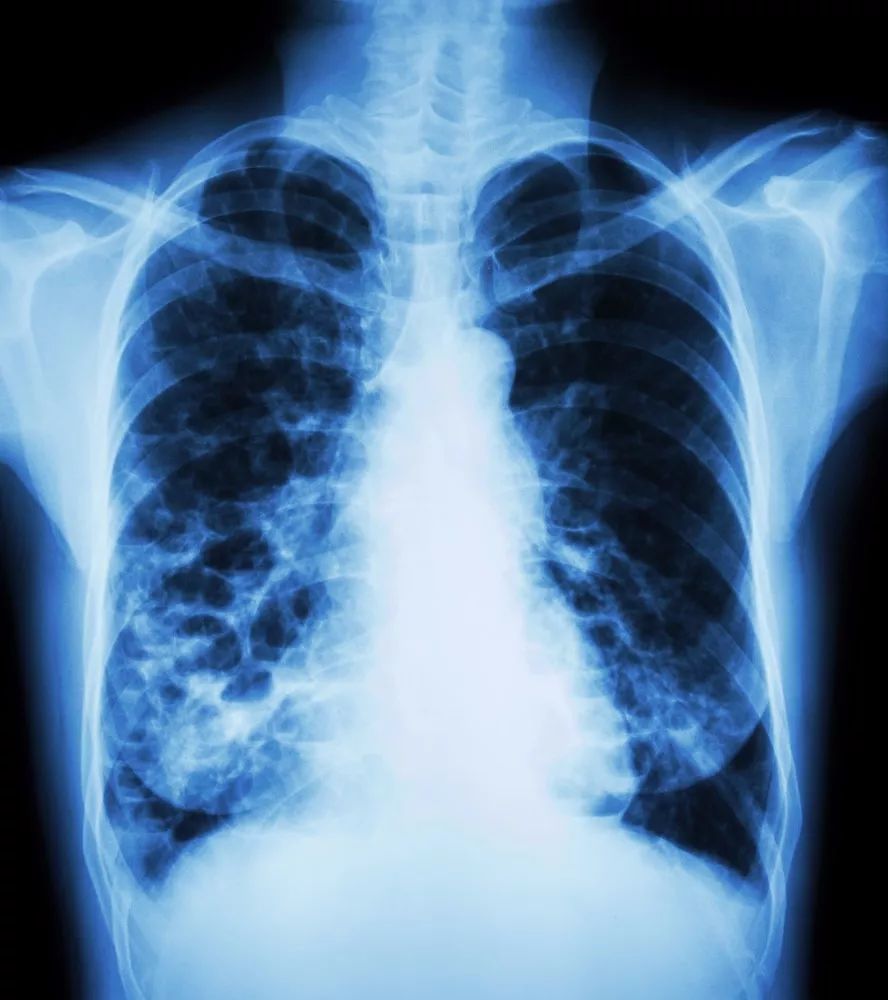

虽然慢阻肺无法彻底治疗,但只要及早发现及治疗,是可以通过生活及药物治疗,阻止疾病的发展。药物治疗可改善症状,稳定肺功能,提高日常生活质量,延长寿命。

慢阻肺可以防可治,但无法完全治愈,慢阻肺的治疗目标是缓解症状,防止进展,另外,慢阻肺还可能伴发一系列严重的合并症,坚持长期药物治疗和预防是控制慢阻肺疾病进展的关键。